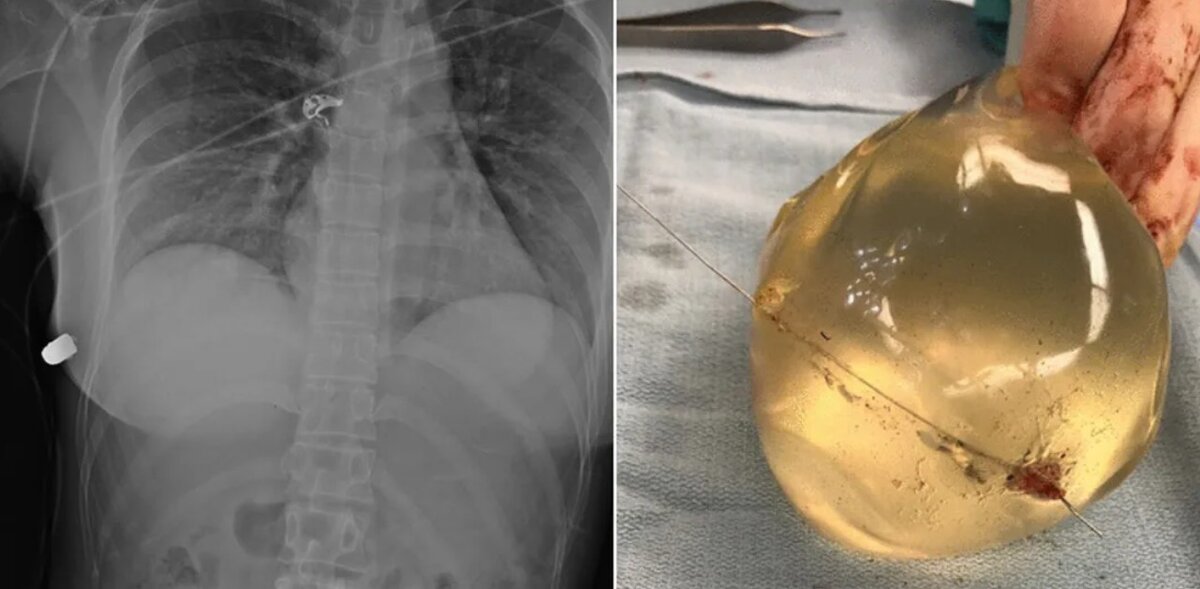

- типу наполнителя (обычно это солевый раствор или силикон);

- форме (она может быть круглой, или анатомической; круглая помогает создать эффект пуш-ап, а анатомическая создает естественный вид бюста);

Главная причина того, почему так важно максимально серьезно подходить к вопросу выбора грудного импланта – это исключение риска осложнений.